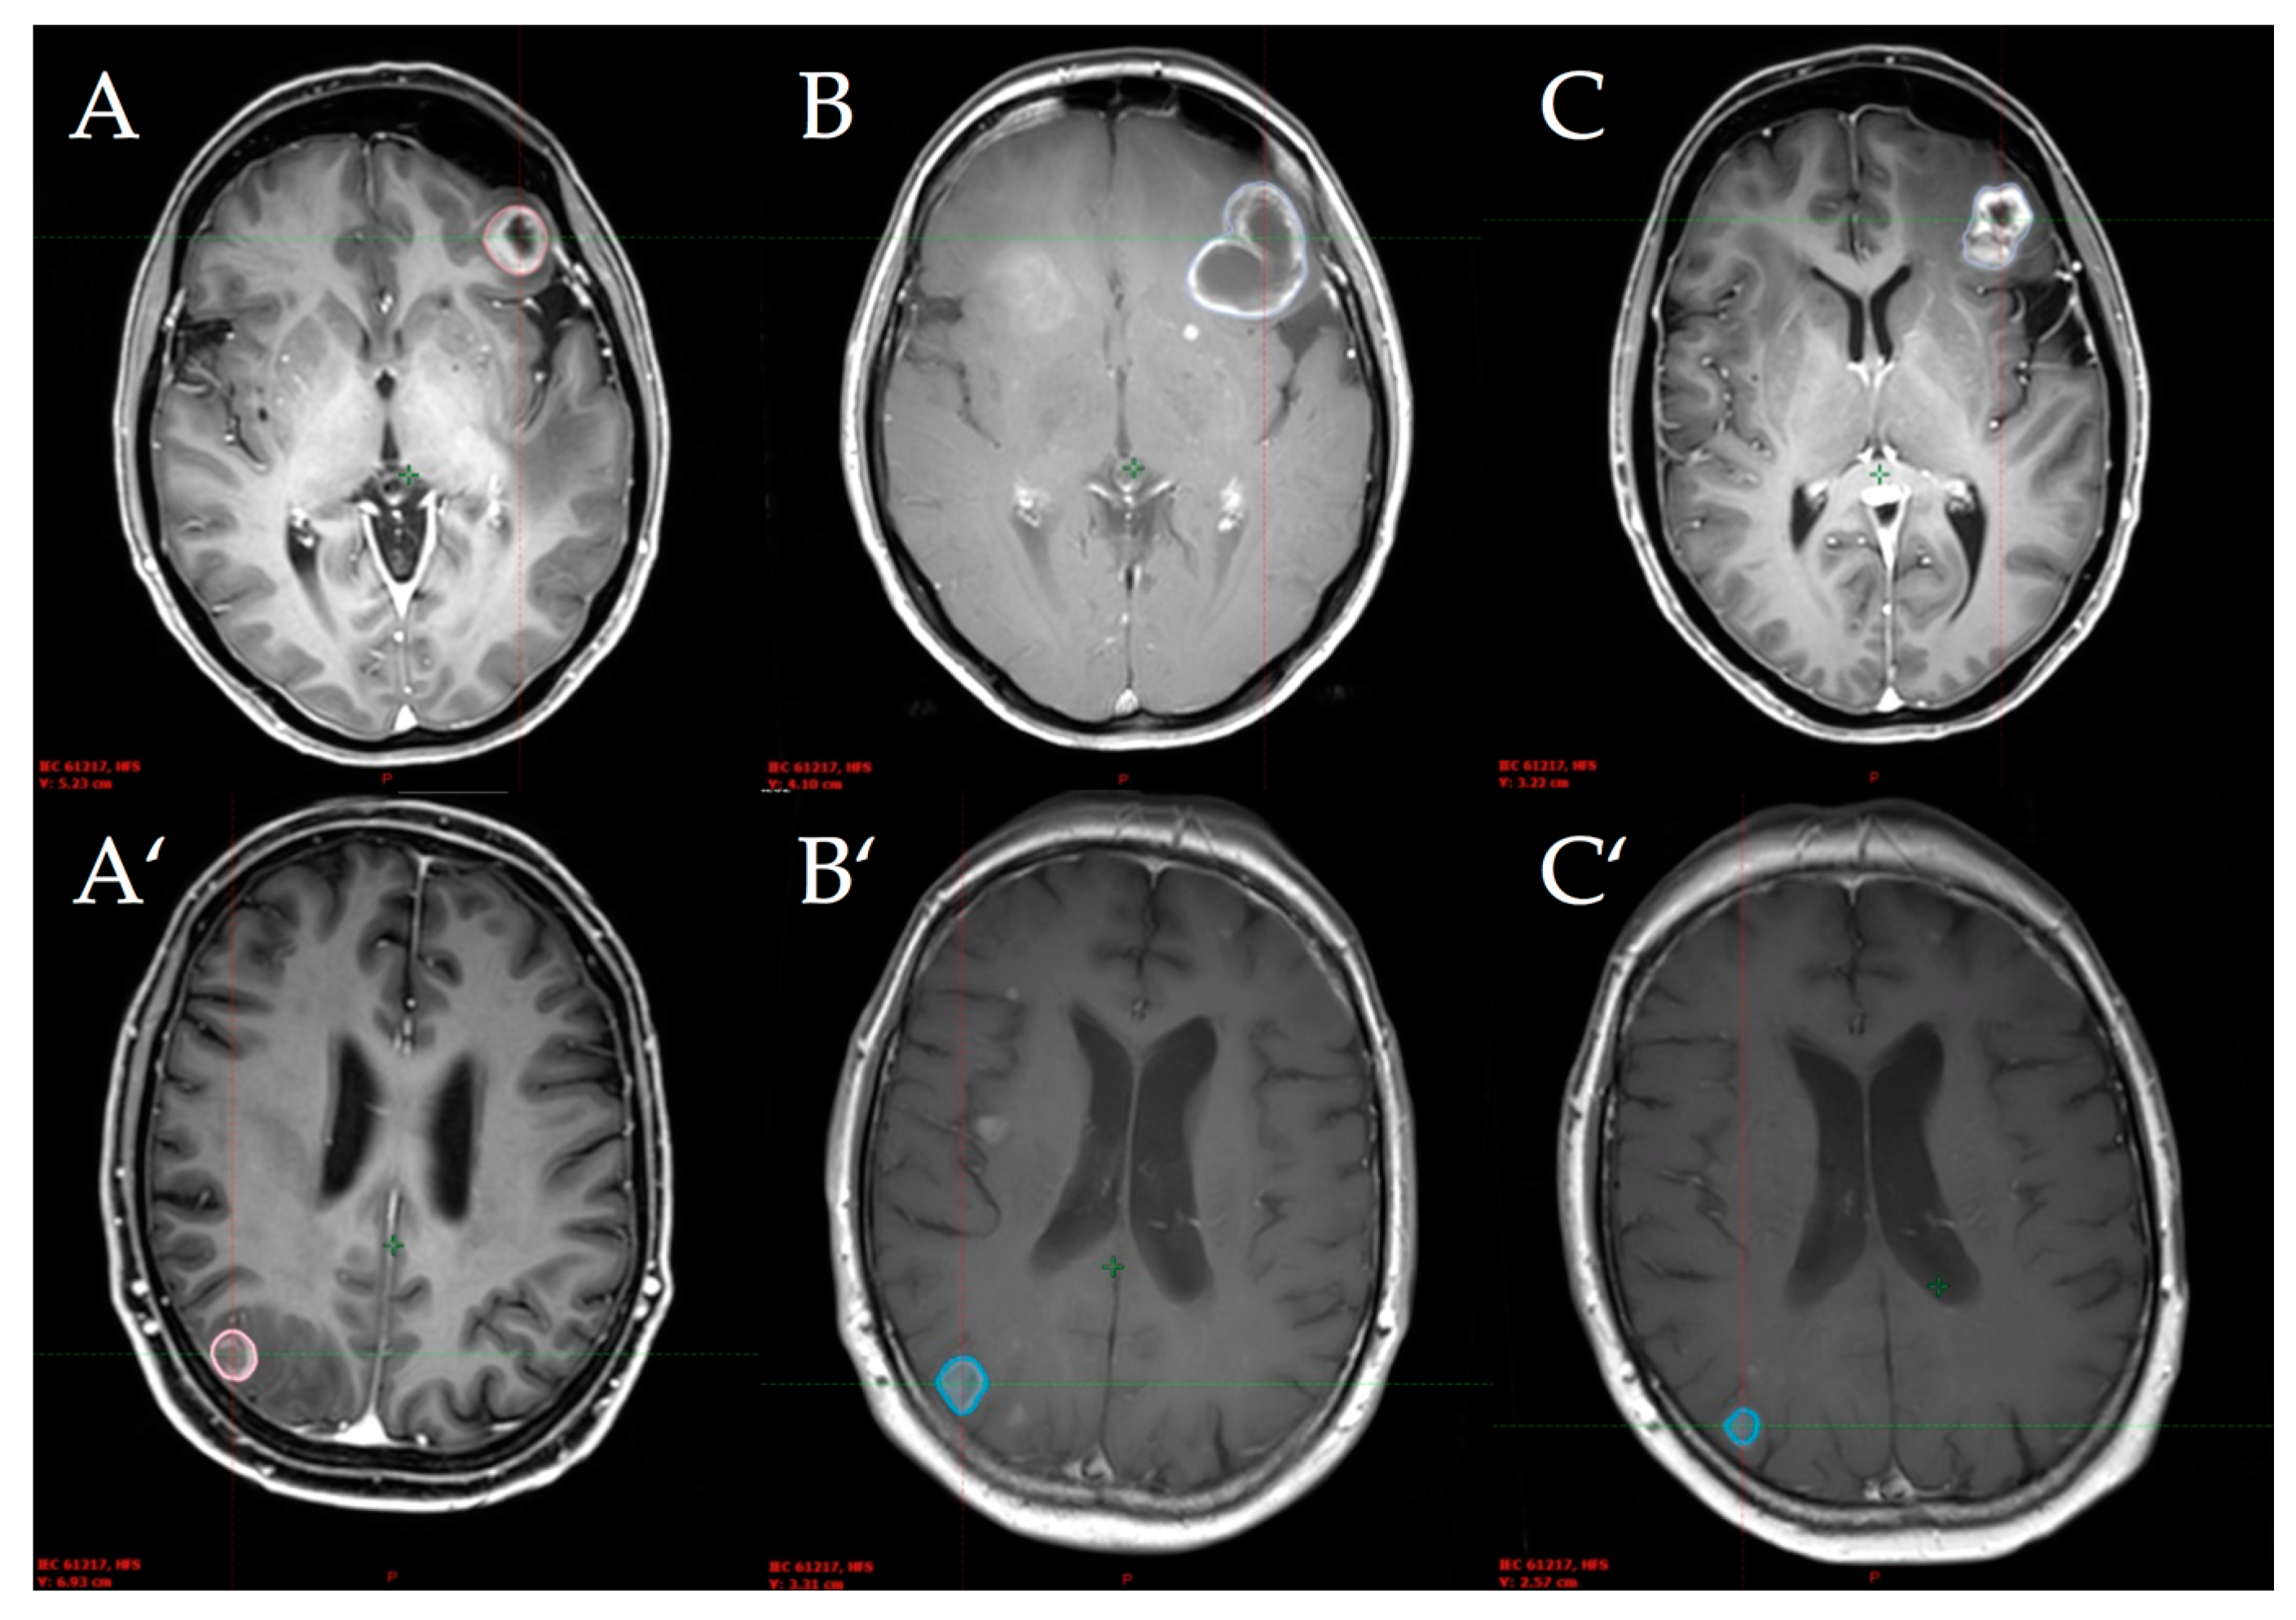

The radiological images of two simultaneously treated patients with an initial increased volume and subsequent regression are shown in Figure 1.

Figure 1.

Lesion 1 of simultaneously treated patient No. 1 (top) and lesion 2 of simultaneously treated patient No. 4 (bottom) at baseline (A), first follow-up (B), and second follow-up (C) after stereotactic radiosurgery.